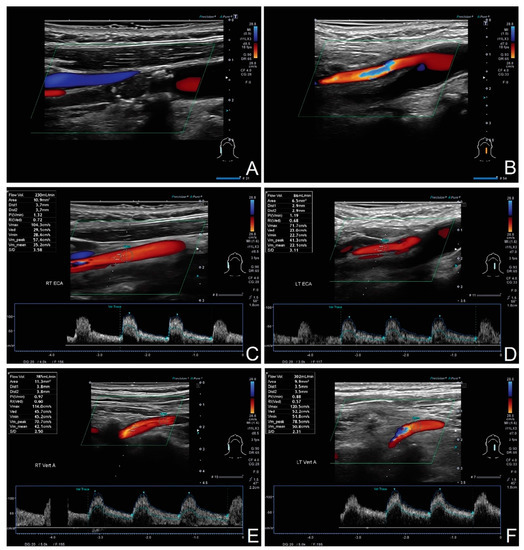

2. Materials and Methods

3.2. The Degree of Compensation in Extracranial Arteries with Compensatory Increased Flow

3.3. The Pathways of Volumetric Flow Compensation in the Extracranial Arteries

- 23 contralateral ICA

- 16 contralateral ECA

- 17 contralateral VA

- 23 ipsilateral ECA

- 22 ipsilateral VA.